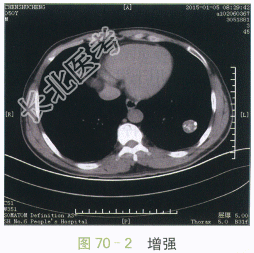

影像学资料如图70-1~图70-4所示。

图70-1~图70-4胸部CT平扫与增强:左肺下叶类圆形肿块,边缘光滑,瘤灶内斑点状钙化,呈爆米花样改变,增强扫描未见明显强化

读片分析:CT表现:左肺下叶类圆形肿块,直径约2.7cm,边缘光滑清楚,瘤灶内见多发的小斑片状钙化,呈爆米花样改变,增强扫描未见明显强化。